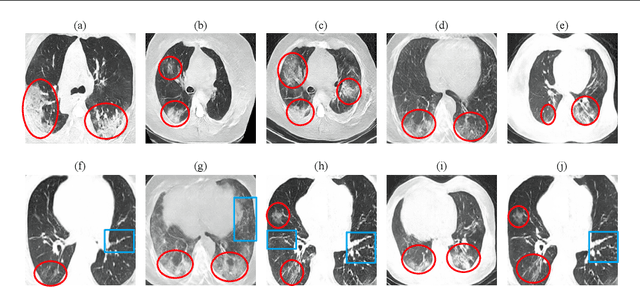

Abstract:Radiographic images offer an alternative method for the rapid screening and monitoring of Coronavirus Disease 2019 (COVID-19) patients. This approach is limited by the shortage of radiology experts who can provide a timely interpretation of these images. Motivated by this challenge, our paper proposes a novel learning architecture, called Detail-Oriented Capsule Networks (DECAPS), for the automatic diagnosis of COVID-19 from Computed Tomography (CT) scans. Our network combines the strength of Capsule Networks with several architecture improvements meant to boost classification accuracies. First, DECAPS uses an Inverted Dynamic Routing mechanism which increases model stability by preventing the passage of information from non-descriptive regions. Second, DECAPS employs a Peekaboo training procedure which uses a two-stage patch crop and drop strategy to encourage the network to generate activation maps for every target concept. The network then uses the activation maps to focus on regions of interest and combines both coarse and fine-grained representations of the data. Finally, we use a data augmentation method based on conditional generative adversarial networks to deal with the issue of data scarcity. Our model achieves 84.3% precision, 91.5% recall, and 96.1% area under the ROC curve, significantly outperforming state-of-the-art methods. We compare the performance of the DECAPS model with three experienced, well-trained thoracic radiologists and show that the architecture significantly outperforms them. While further studies on larger datasets are required to confirm this finding, our results imply that architectures like DECAPS can be used to assist radiologists in the CT scan mediated diagnosis of COVID-19.